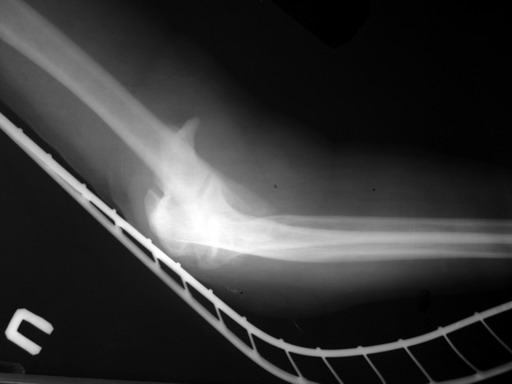

Солидарен с мнением обоих Александров (Челнокова и Рыкова): точную репозицию такого перелома вряд ли удастся выполнить закрыто. Даже во время открытого вмешательства это сделать непросто. Неслучайно предложен костно-пластический доступ с временным отсечением локтевого отростка. И по методу фиксации согласен с Александром Челноковым: 2 пластины. В качестве примера привожу рентгенограммы одного из наших пациентов с аналогичным повреждением.

С уважением, А. Золотов, Приморский край.